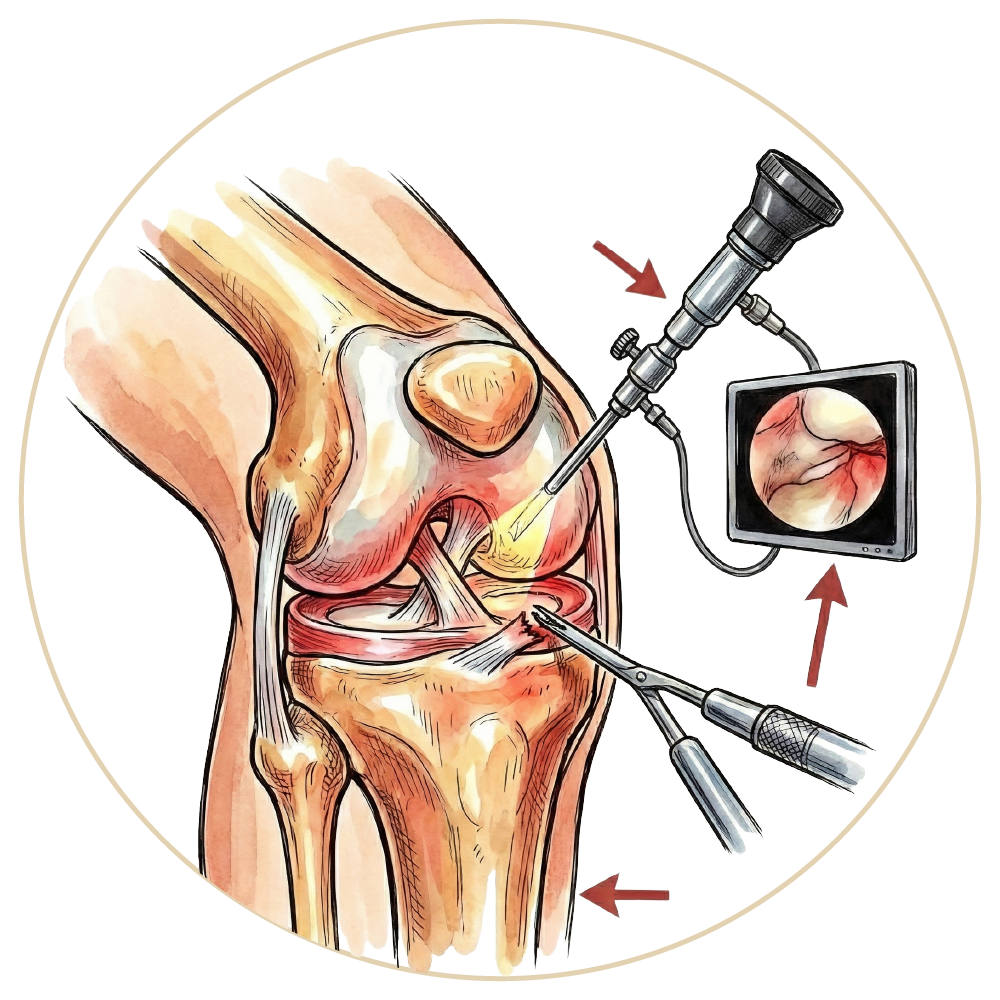

Artroskopi

Diz Artroskopisi